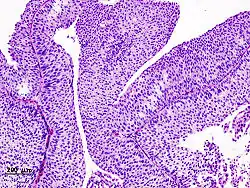

Dysgerminoma | Dysgerminoma characterized by uniform cells resembling primordial germ cells separated by fibrous septa with lymphocytes. | Category: Histopathology of ovarian dysgerminoma | Ovarian dysgerminoma |

![]() |